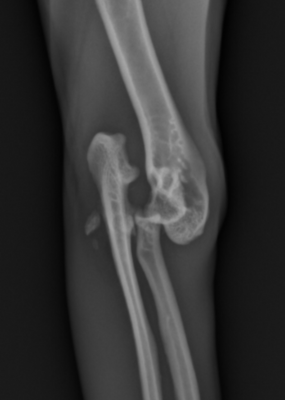

Le diagnostic repose sur des radiographies ciblées :

- Face : met en évidence le décalage latéral du radius et de l’ulna

- Profil : évalue la hauteur du déplacement et détecte d’éventuelles fractures

- Vues obliques : parfois nécessaires pour identifier une luxation latérale isolée

Ces examens servent aussi à planifier le traitement, conservateur ou chirurgical.